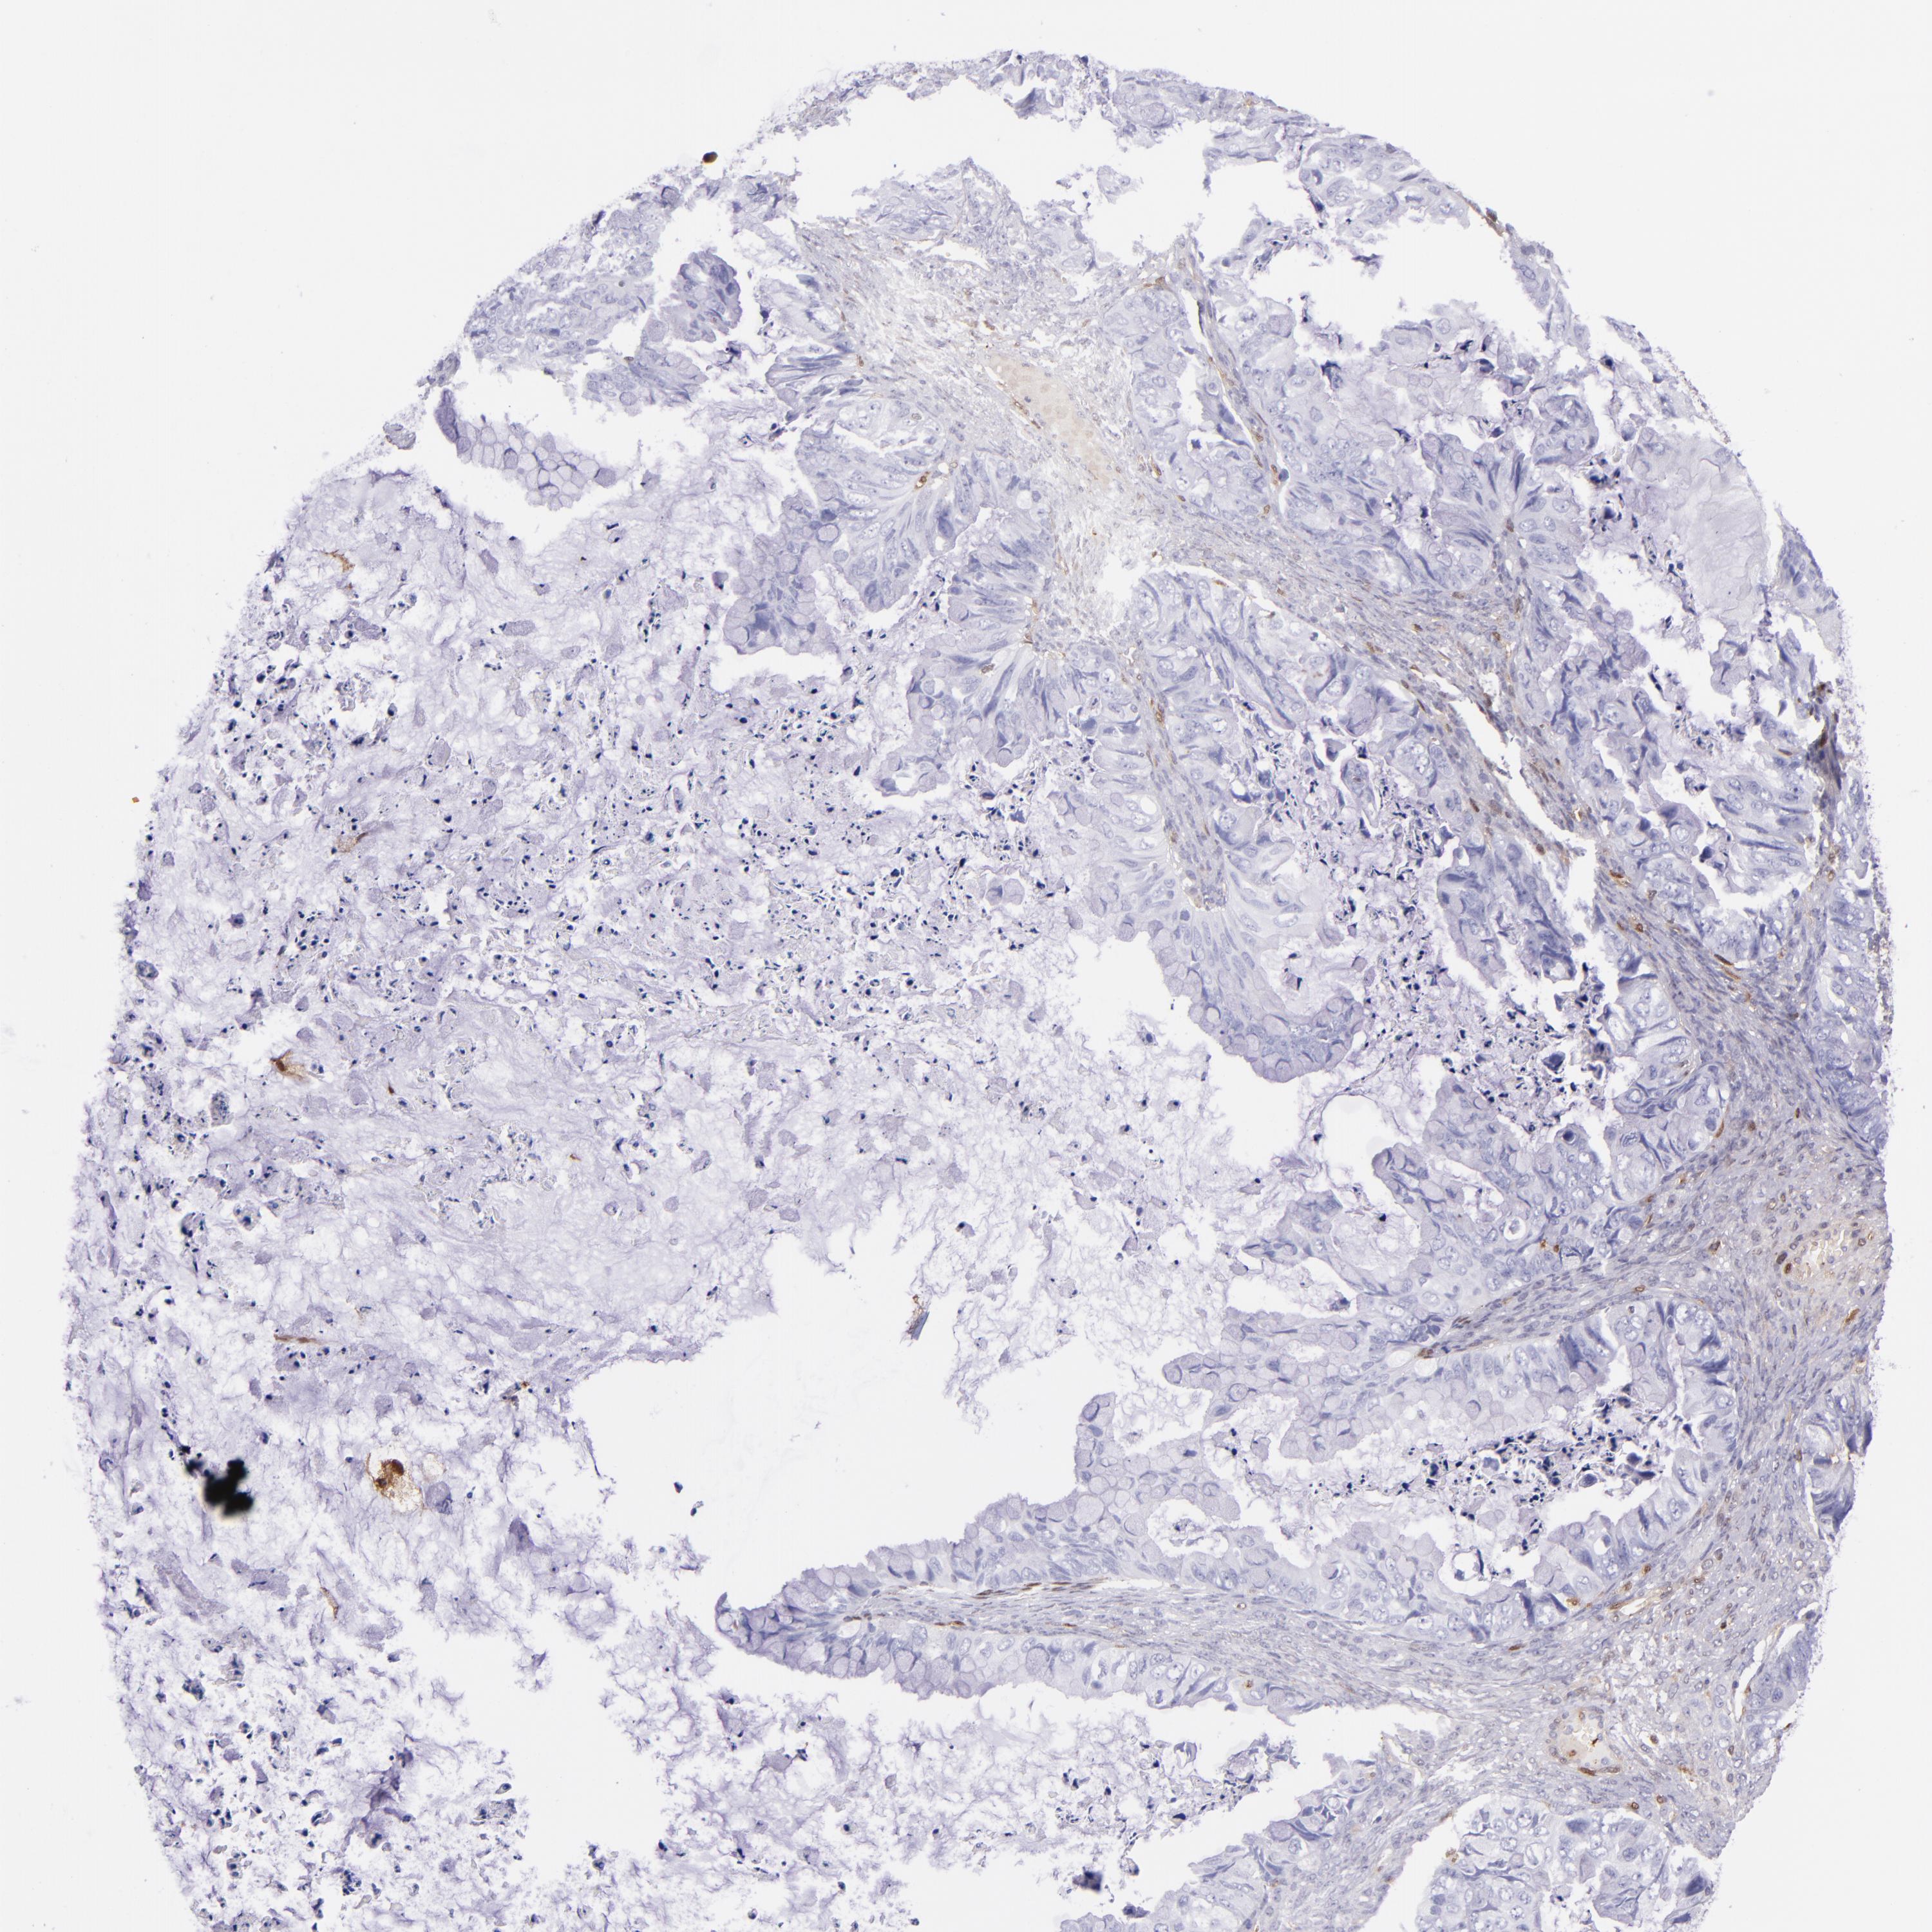

OVARIAN CANCER - Protein expressioni

A mouse-over function shows sample information and annotation data. Click on an image to view it in a full screen mode. Samples can be filtered based on level of antibody staining by selecting one or several of the following categories: high, medium, low and not detected. The assay and annotation is described here.

Note that samples used for immunohistochemistry by the Human Protein Atlas do not correspond to samples in the TCGA dataset.

Antibody stainingi

Antibody staining in the annotated cell types in the current human tissue is reported as not detected, low, medium, or high, based on conventional immunohistochemistry profiling in selected tissues. This score is based on the combination of the staining intensity and fraction of stained cells.

Each image is clickable and will lead to virtual microscopy that enables deeper exploration of all samples and also displays staining intensity scores, fraction scores and subcellular localization as well as patient and tissue information for each sample.

Antibody HPA000646

Carcinoma, endometroid

Cystadenocarcinoma, serous, NOS